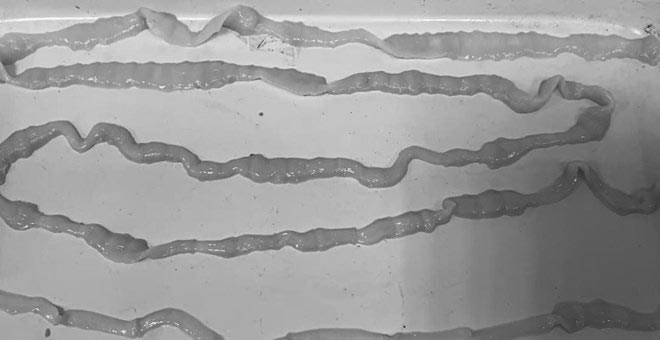

Hình ảnh một bệnh nhân nhiễm giun sán, sán dây 10m. Ảnh: Lệ Hà